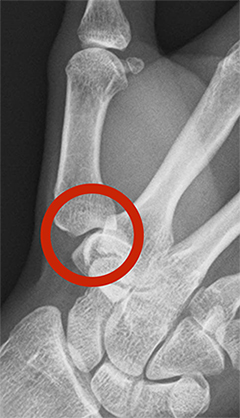

正常な母指CM関節

軟骨が減り、変形している母指CM関節